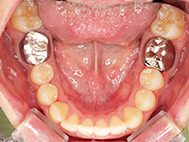

After

| 症状 | 上顎前歯部叢生 |

上の前歯がハの字隣の歯が引っ込んでいる

前歯のガタガタが気になるとの事で来院されました。

装着が目立ちたくないとの事でアライナ-での矯正を希望されました、歯の間を削り少し歯の幅をスリムにして綺麗なアーチに並びました。